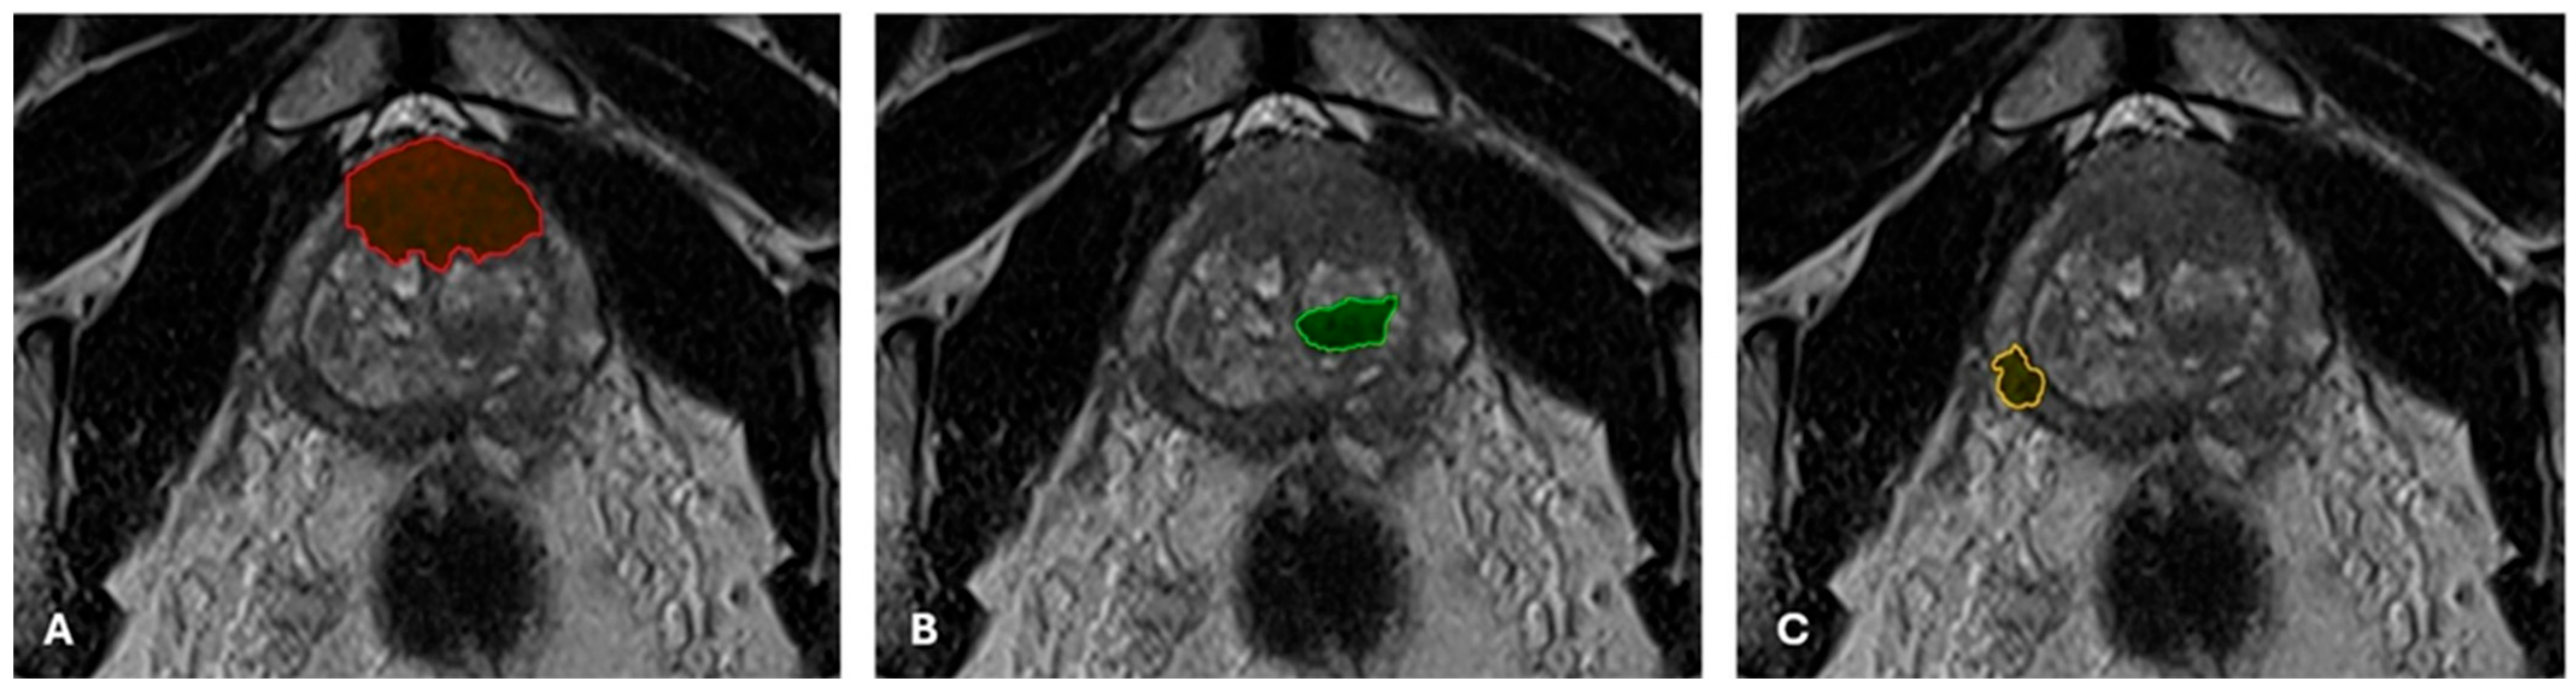

2.3. Oblique-Axial T2WI Segmentation